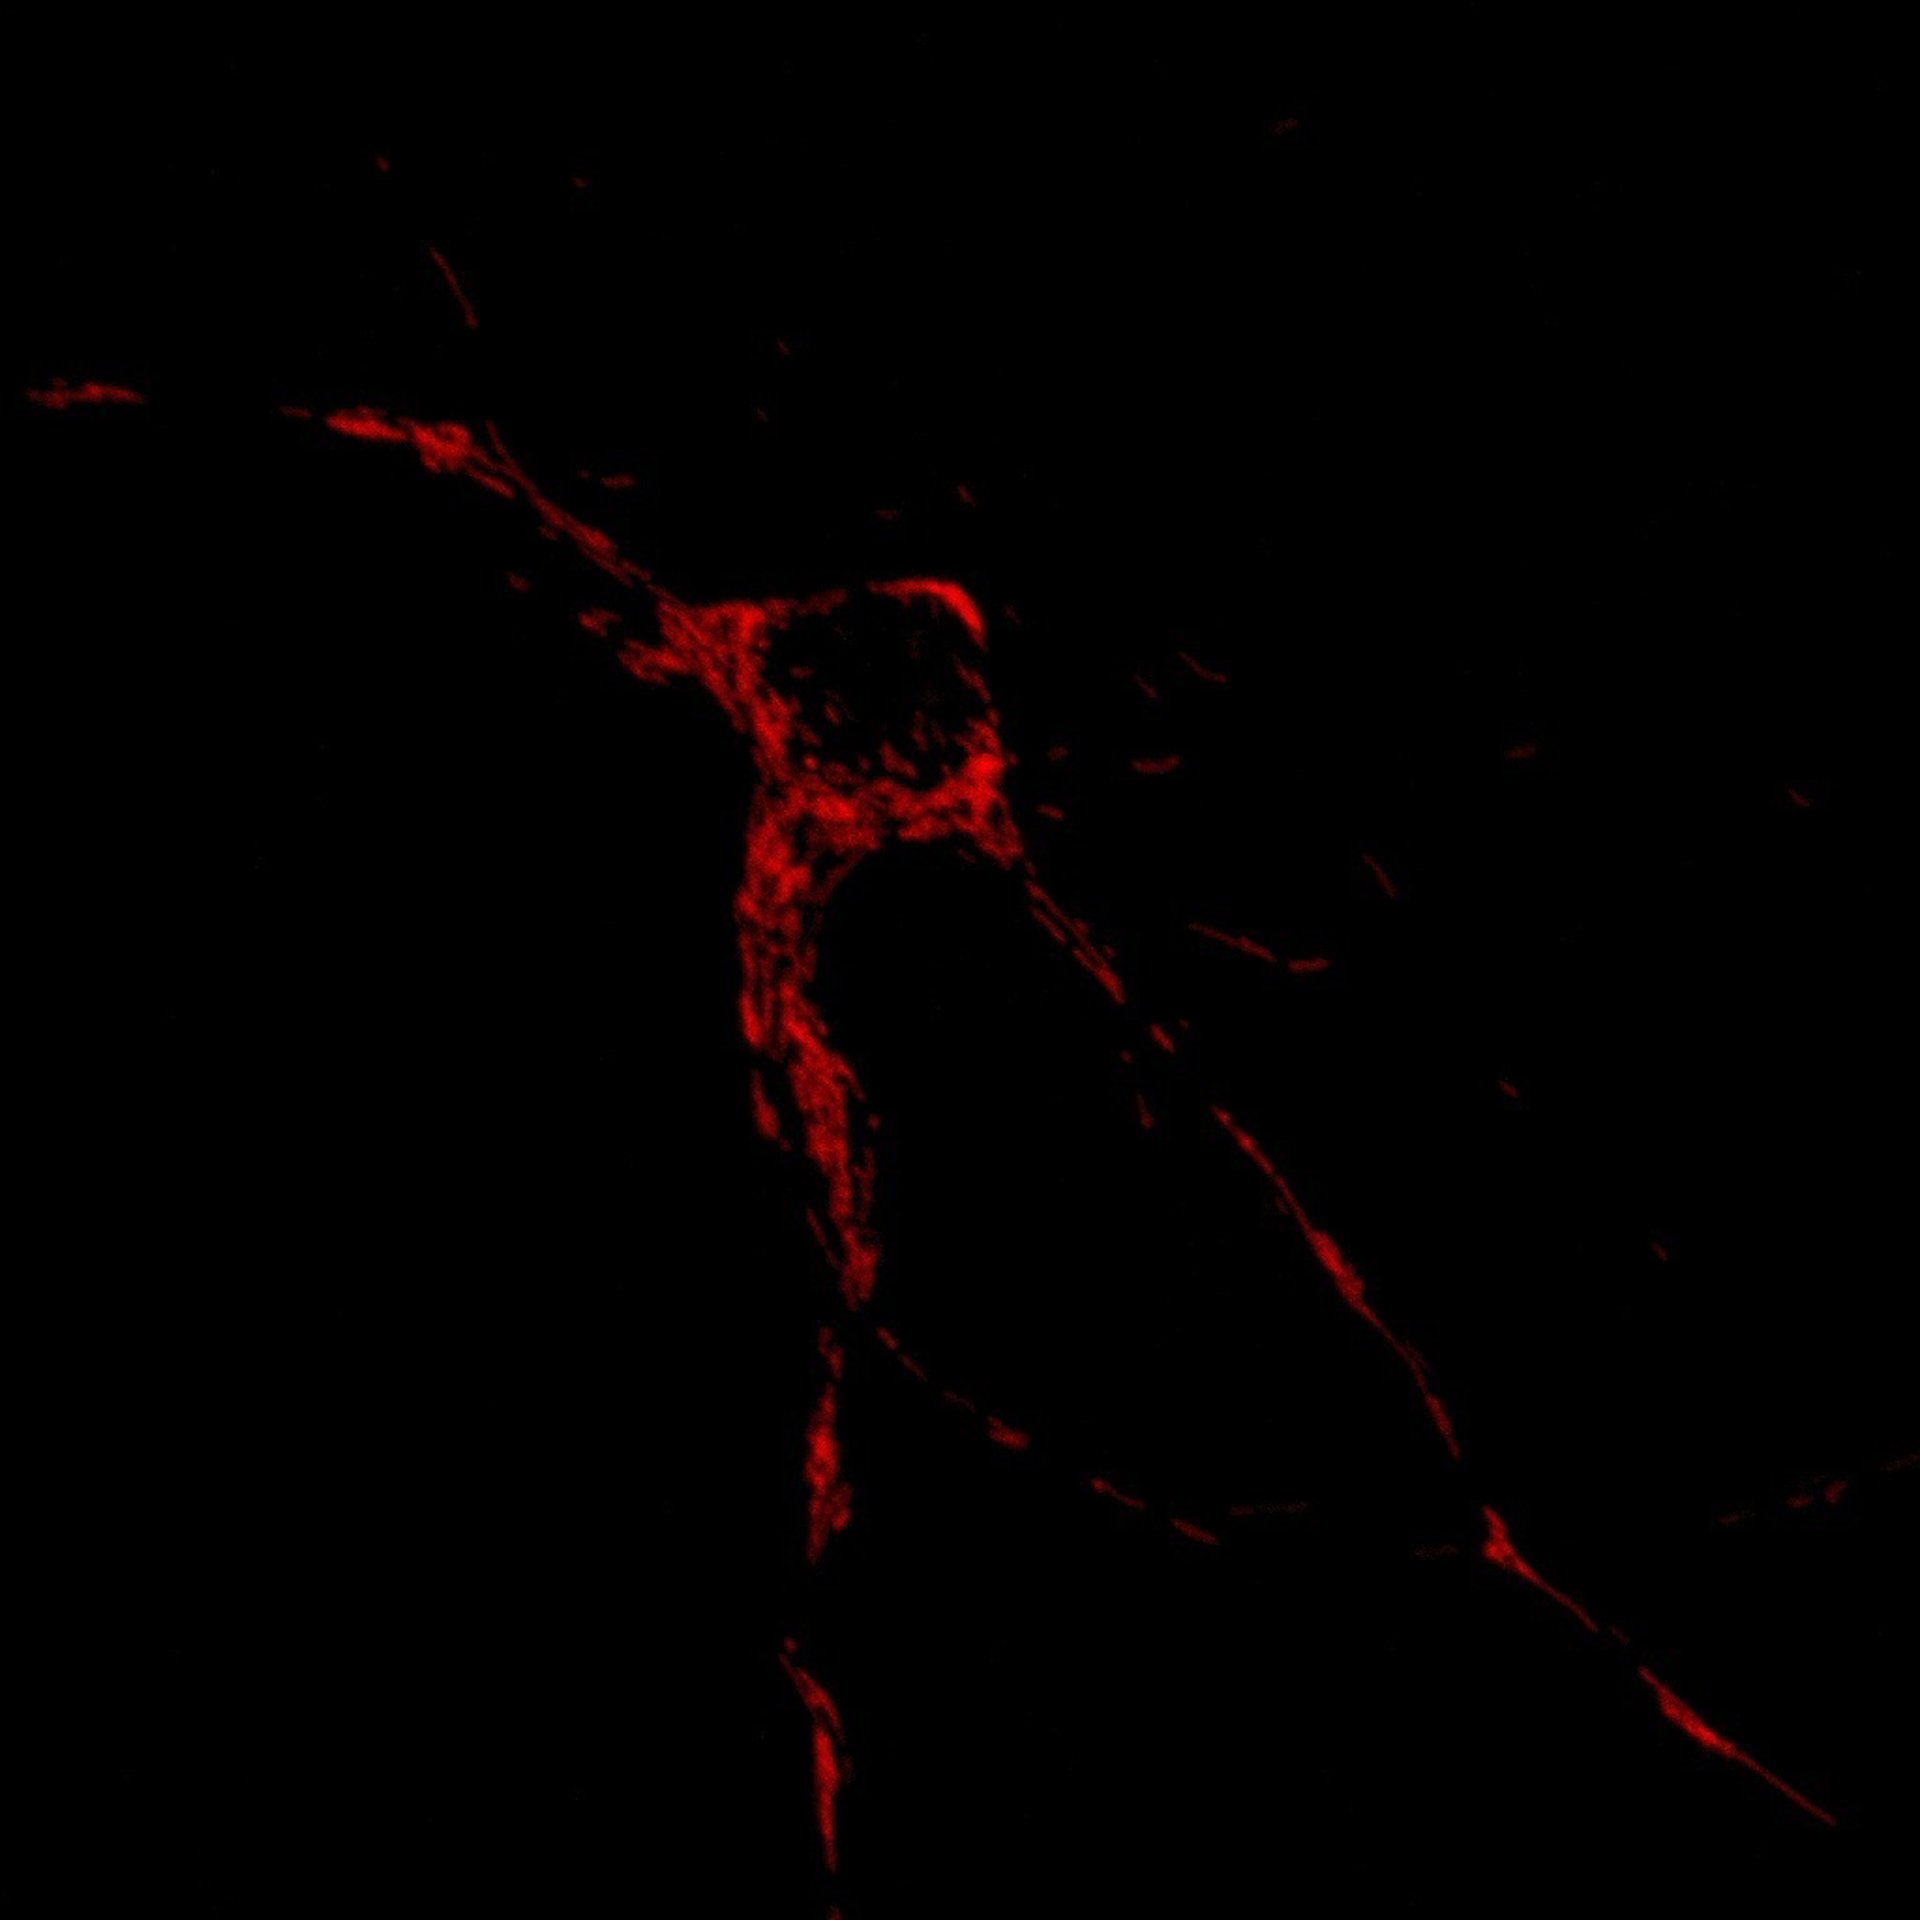

En Rojo, Localización De Mitocondrias En Una Neurona

Científicos del Instituto de Investigación Biomédica (IRB) de Barcelona han logrado identificar un grupo de seis genes cuya función es regular el movimiento y posición de las mitocondrias en las neuronas, un papel clave en el funcionamiento y viabilidad del cerebro.

El cerebro requiere de una gran cantidad de energía para funcionar, ha recordado el IRB en un comunicado, pero dicha energía debe ser distribuida a lo largo de las neuronas, unas células que tienen ramificaciones que pueden llegar a ser de decenas de centímetros desde el cerebro hasta las extremidades.